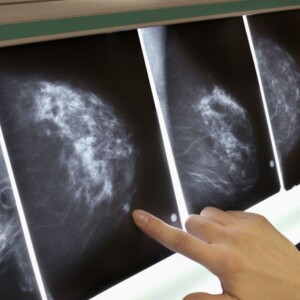

У сучасній медицині для профілактичної діагностики грудей лікарі застосовують апарат мамограф. Мамографія – це найточніший метод дослідження, що дозволяє візуалізувати структури молочних залоз. Таким чином, лікар може виявити кісти або інші новоутворення в органі.

- Мамографія. Фахівець проводить скринінг молочної залози. Якщо на маммограмі буде виявлено аномалію, лікар порекомендує додаткове обстеження.